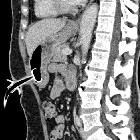

On occasion it is necessary to image for complications of PEG tubes - either immediately after insertion or when long standing. The typical clinical problem relates to concerns over displacement, including buried bumper syndrome.

Occasionally contrast will be injected via the PEG to determine its position, a so-called PEGogram.